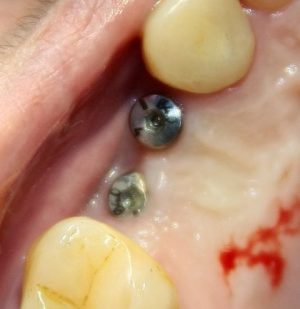

Поэтому после удаления зуба мы ждём, в общей сложности, около 4-8 недель, затем приступаем к имплантологическому лечению. Хотя, иногда бывают ситуации, когда мы делаем синуслифтинг одномоментно с удалением зуба, а сам имплантат ставим попозже:

через 4 месяца: